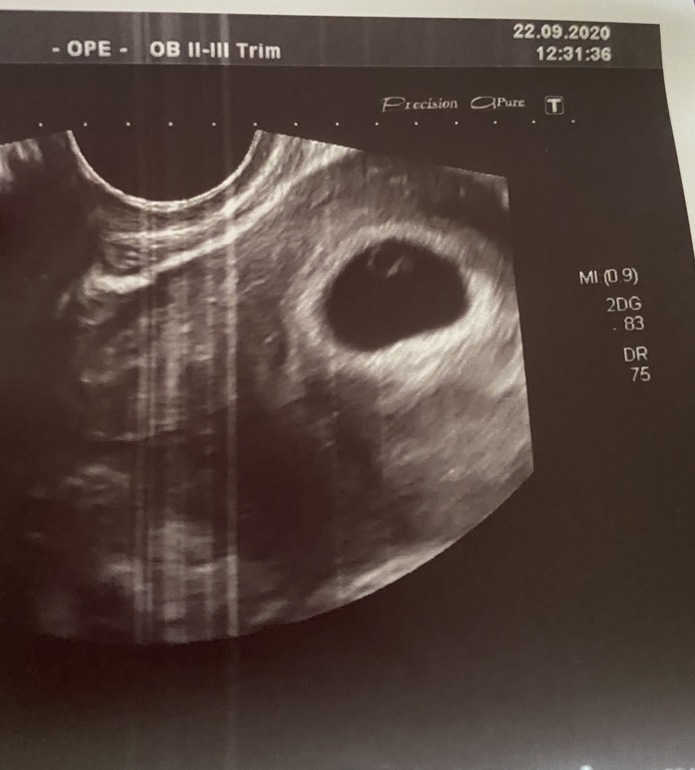

Беременность- 1 триместр ( только до 10 недель)Не выдержала душа поэта и сходила я на узи (хотя планировала 28 сентября идти на первое узи),

Итог: по менструации 6 недель 4 дня, с учетом овуляции 6 недель 1 день, по узи (ктр) ровно 6 недель и мы увидели сердцебиение !!!!!!! Допплер не стали включать, но это трепыхание увидели все 😍